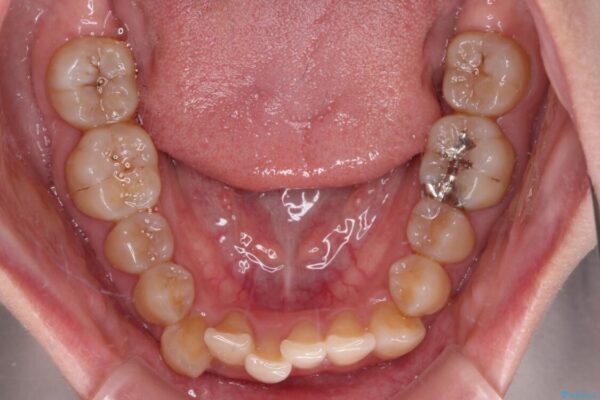

下顎の八重歯を気にして来院された患者様です。

下顎前歯にデコボコが集中していたため、顎間ゴムによる後方移動とIPR(歯と歯の間を削ること)により歯列を整えることとしました。

治療前、下顎前歯のデコボコが集中しており、奥歯の咬み合わせは、上顎に対して下顎が前方位にある状態でした。下顎の歯列を後方へ移動させる治療はインビザラインの得意とするところですので、1年程度で無事に治療を終えることができました。

治療途中

• 【モニター】下顎前歯のデコボコをインビザラインできれいに 治療途中画像